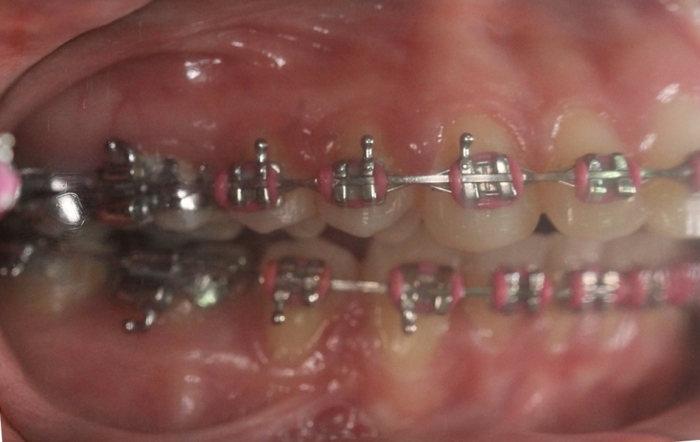

Mordida após a cirurgia